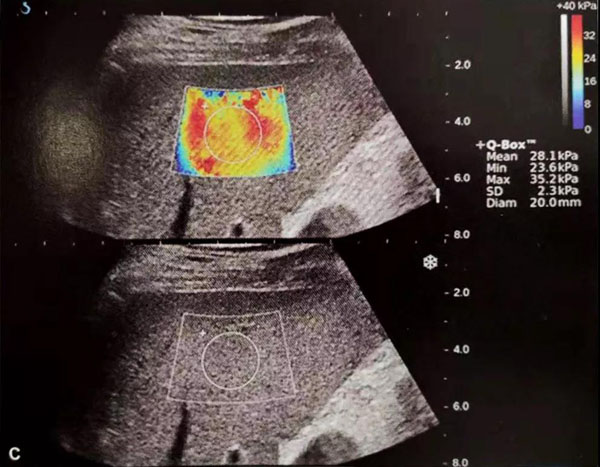

“E超”是一种全新的超声成像模式,具有独有的极速E-成像技术,能够实时、全幅、全定量的进行软组织硬度测量剪切波弹性成像,用超声波触诊内脏器官的硬度,并通过不同的颜色和精确地硬度值来反应所“触诊”部位的硬度,完成传统超声(B超)不能实现的组织定性分析,得到组织的弹性模量绝对值,真正实现无创、超声弹性成像定量分析,为鉴别肿瘤的良恶性提供客观、量化的诊断依据,可减少80%不必要穿刺,是目前世界上先进的新型超声诊断技术。

<E超检查肝脏的图像>

“E超”在各个学科已有广泛应用,它能够对肝脏、胰腺、脾脏、肾脏、前列腺、子宫、卵巢、甲状腺、乳腺、淋巴结、肌肉、肌腱、血管、神经、淋巴结等组织器官进行弹性定量分析。可以全面应用于乳腺、甲状腺、肝脏、前列腺等人体各组织器官筛查,鉴别良、恶性肿块的性质,与病理学切片相媲美,避免组织穿刺活检细胞学分析的痛苦。